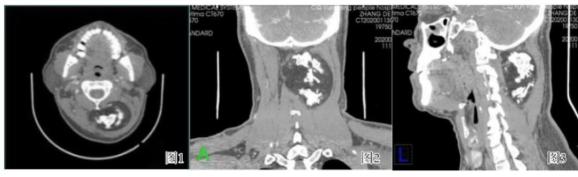

成人颈项部间叶性错构瘤CT增强图像。来源丨向武昌,杨小蓉. 成人颈项部间叶性错构瘤一例[J]现代医用影像学. 2021,30(04).虽然错构瘤发病率小,并且常见发现于婴儿或儿童时期。但也有特例发生在成人时期。

所以不论处在人生的哪一个阶段,都要注意观察自己的身体是否出现了异常的变化,出现了异常变化或身体感觉明显不适就要及时就医,以免出现更严重的后果。